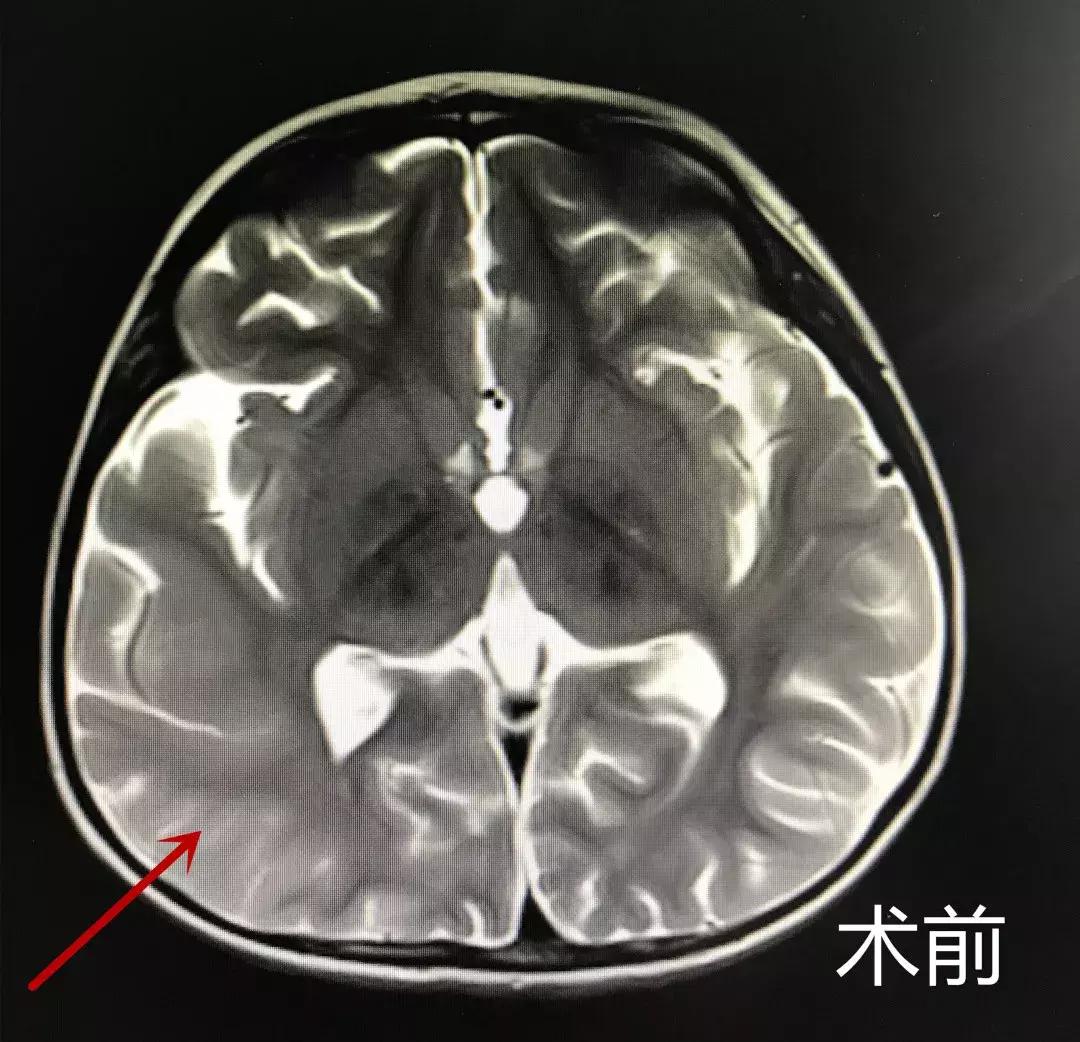

这样的情况已经发生了很多次。四肢不对称强直抽搐,头偏向右侧,人事不省,呼之不应。虽然持续时间短,但发作异常频繁,一天约数十次。仅3岁的小蕊时常是“冷不丁”地发作,严重影响了她的生活,用她妈妈的话说,“折磨得都快没有人样了”。

术前

林志雄教授细细询问病史,查看检查结果后,告知小蕊家人,考虑是:巨脑回畸形、灰质异位导致难治性癫痫。

通过与北京三博癫痫中心团队进行多学科讨论后决定行“右侧颞叶切除,颞顶叶离断术”。手术顺利结束后,目前小蕊已转回普通病房,一天数十次的发作神奇般的消失了。